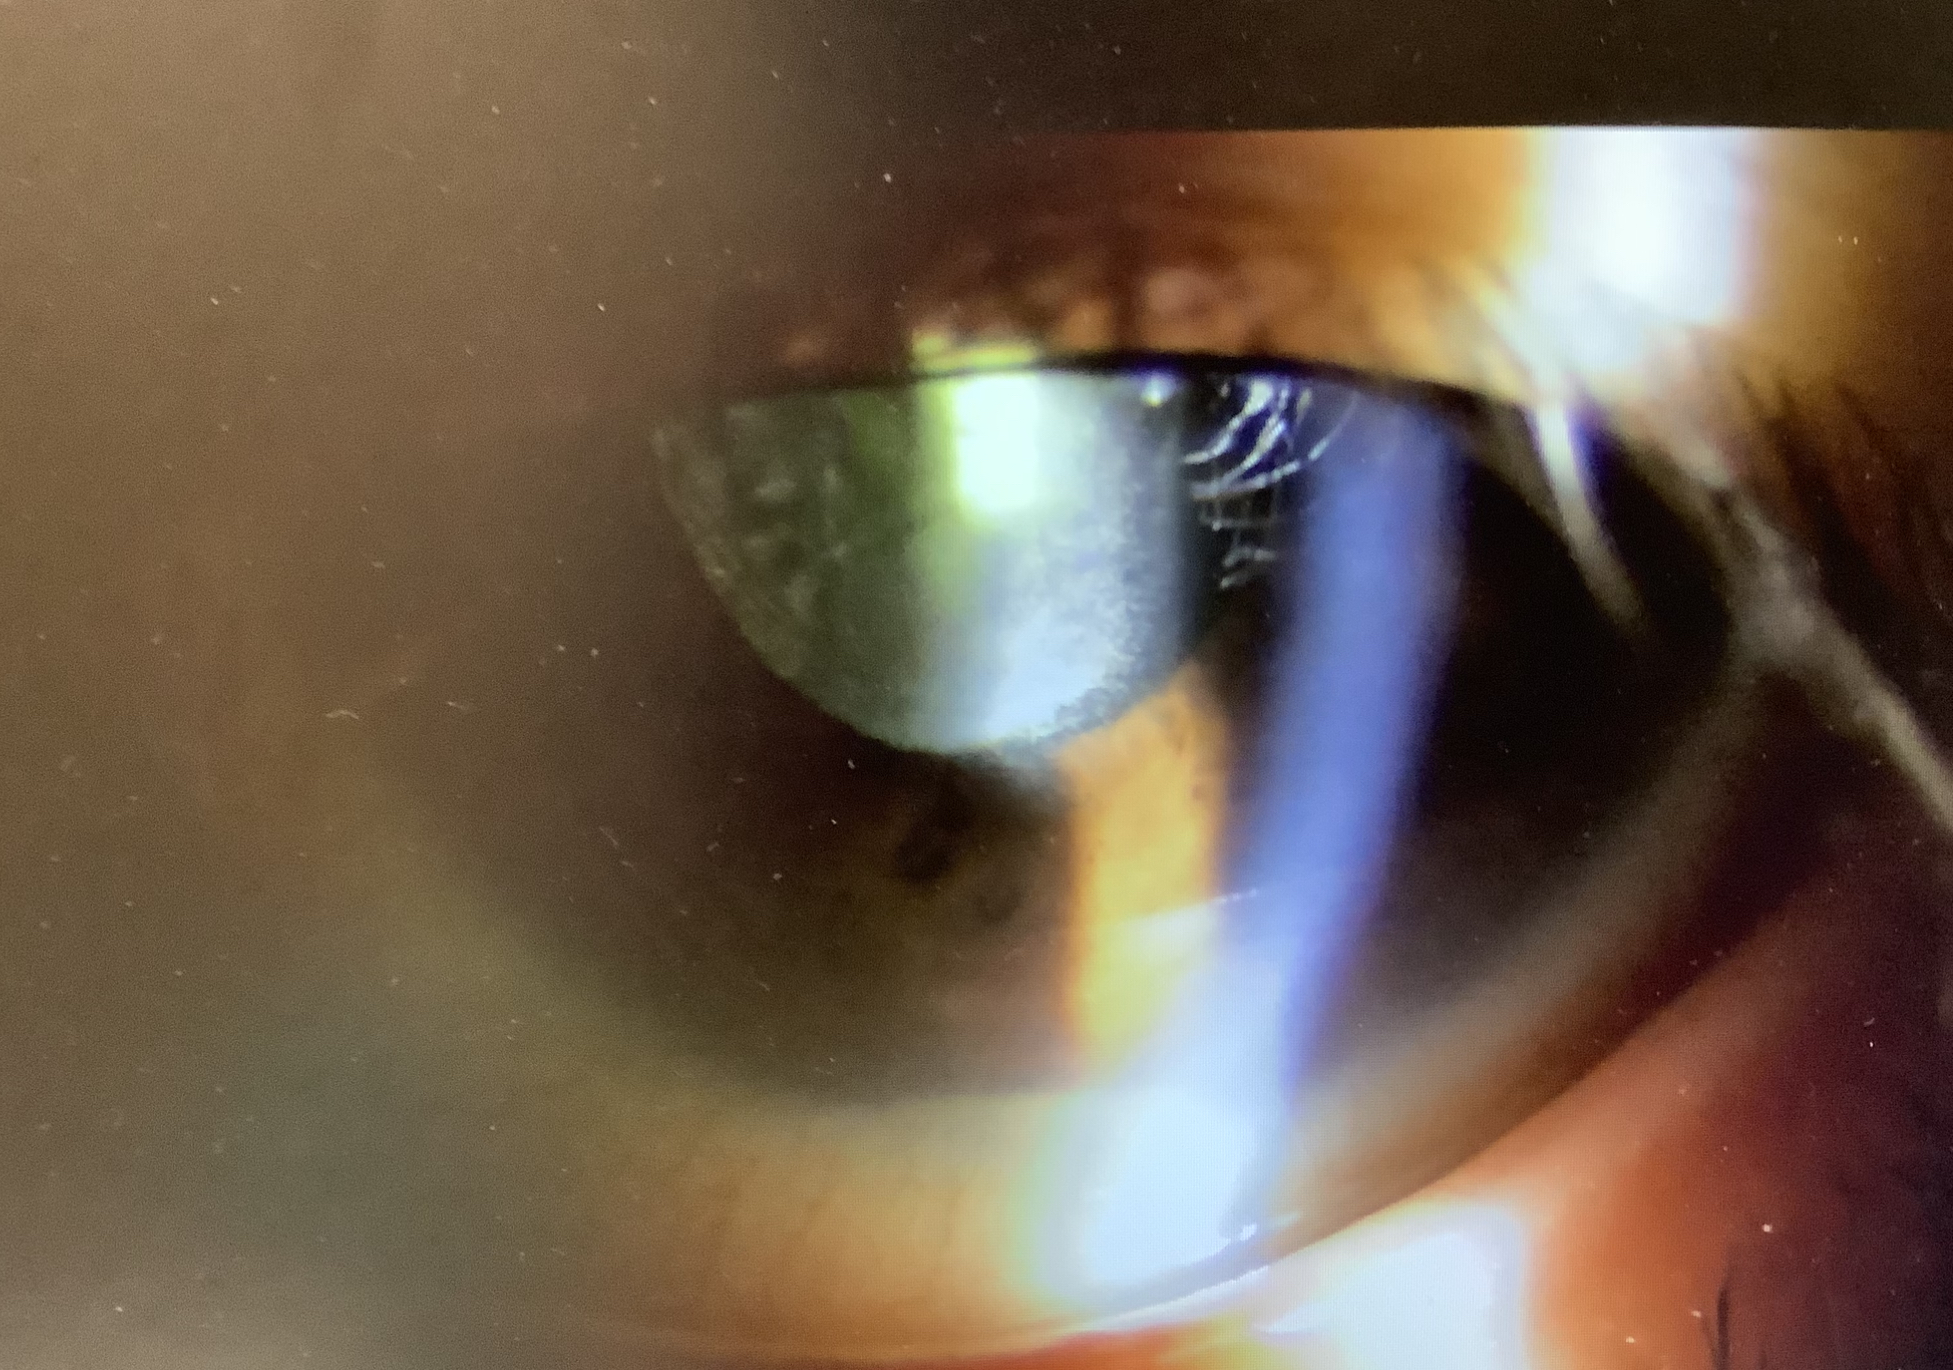

その中で、水曜日に左眼の手術をした70代の男性の方は、炎症細胞が強く出ており、瞳孔にもフィブリンが張っているような状況で、”眼内炎“という状態と考えられました。炎症の原因が細菌などの感染によるもの(感染性眼内炎)と感染以外の原因(無菌性眼内炎)とがありますが、術翌日は問題なく、ご本人に自覚も徐々に見えにくくなってという経過から、おそらくは感染性の眼内炎と思われました。硝子体までは炎症が及んでいないと思われましたので、今日は眼の中の前のスペースを洗浄(前房洗浄)し、硝子体に抗菌薬の注射をする処置を緊急でさせていただきました。